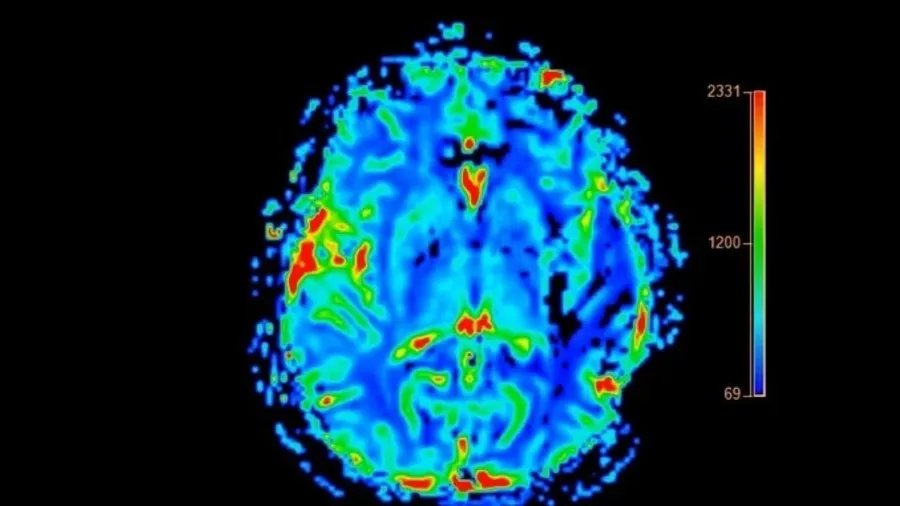

ABD’de yaklaşık 7 milyon kişiye demans teşhisi konuldu. Bu nörolojik hastalık, hafızayı, düşünme becerilerini ve günlük yaşam aktivitelerini kademeli olarak yok ediyor. Demans türleri arasında Alzheimer en yaygın olanı olmaya devam ederken, daha az bilinen ancak dikkat çekici belirtilerle seyreden bir tür daha var: Lewy cisimcikli demans (LBD). Uzmanlara göre, bu hastalık Alzheimer’dan farklı olarak özellikle duruş bozuklukları ve halüsinasyonlarla kendini gösterebiliyor.

Michigan Nörolojik Bozukluklar Enstitüsü’nden (MIND) Dr. Jonathan Fellows, LBD ile Alzheimer arasında belirgin klinik farklar olduğunu söylüyor. Dr. Fellows, “Hastalar bilişsel yeteneklerinde, uyanıklık ve dikkat seviyelerinde saatlik değişimler yaşayabilir. Bu dalgalanmalar LBD’nin ayırt edici özelliklerinden biridir” ifadelerini kullandı.

HAFIZA YERİNDE AMA HATIRLAMAK ZOR LBD hastaları Alzheimer’ın aksine yeni anılar oluşturabiliyor, ancak bu anıları hatırlamakta zorlanıyorlar. Aynı zamanda hastalık sürecinde detaylı görsel halüsinasyonlar ve REM uykusu davranış bozuklukları da sık görülüyor. Araştırmalara göre, LBD hastaları rüyalarını uykuda bağırarak, tekme atarak ya da yumruk savurarak canlandırabiliyor. Bu davranışlar, bilişsel semptomlardan yıllar önce başlayabiliyor.

TEŞHİSTEN SONRA ORTALAMA YAŞAM SÜRESİ 5-8 YIL Fellows, LBD’nin Alzheimer’dan daha hızlı ilerlediğini ve tanı konulduktan sonra hastaların ortalama 5 ila 8 yıl arasında yaşadığını belirtiyor. Alzheimer hastalarında ise bu süre 8 ila 10 yıl arasında değişiyor. 2014 yılında yaşamını yitiren dünyaca ünlü aktör Robin Williams’ın otopsi raporunda, ölümünden önce LBD hastalığı ile mücadele ettiği ortaya çıkmıştı.

TEDAVİ SEMPTOM YÖNETİMİNE ODAKLANIYOR LBD’nin kesin bir tedavisi bulunmuyor. Tedavide kullanılan yöntemler, semptomları hafifletmeye yönelik. Rivastigmin ve donepezil, beyindeki sinir hücreleri arasındaki iletişimi destekleyen ilaçlardır. Bu ilaçlar; hafıza sorunları, dikkat eksikliği ve halüsinasyonlar gibi belirtilerin azaltılmasına yardımcı olabilir.

LBD hastalarında Parkinson hastalığına benzer titreme, kas sertliği ve yavaş hareket etme gibi semptomlar da görülebilir. Bu tür şikayetler için levodopa (Sinemet) adlı ilaç kullanılabiliyor. Bu ilaç, hareket bozukluklarını hafifletmeye yardımcı oluyor. REM uyku bozukluğu için melatonin veya klonazepam gibi ilaçlar önerilebiliyor. Uzmanlar, LBD’ye benzer belirtiler gösteren kişilerin vakit kaybetmeden bir nöroloji uzmanına başvurmaları gerektiğini vurguluyor.